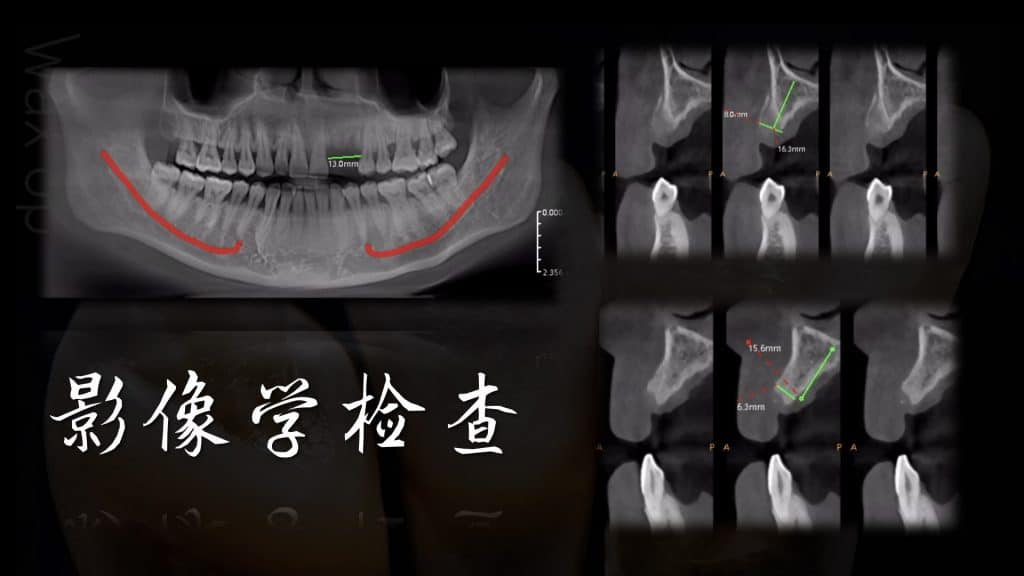

Before the start of this case, we did a fine digital design, including the design and production of temporary teeth, then CBCT matched the oral scan, designed the implant position, designed the incision method of our gums, and then implanted, and immediately repaired after completion, made a personalized gingival counter, and made a permanent restoration after 3 months.